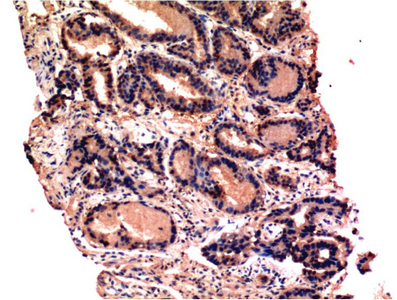

Caspase-3 mouse Monoclonal Antibody(4B8)

Application

| IHC-P |

| Dilution | IHC-P~~IHC 1:100-200 |

| Reactivity | Human, Rat, Mouse |